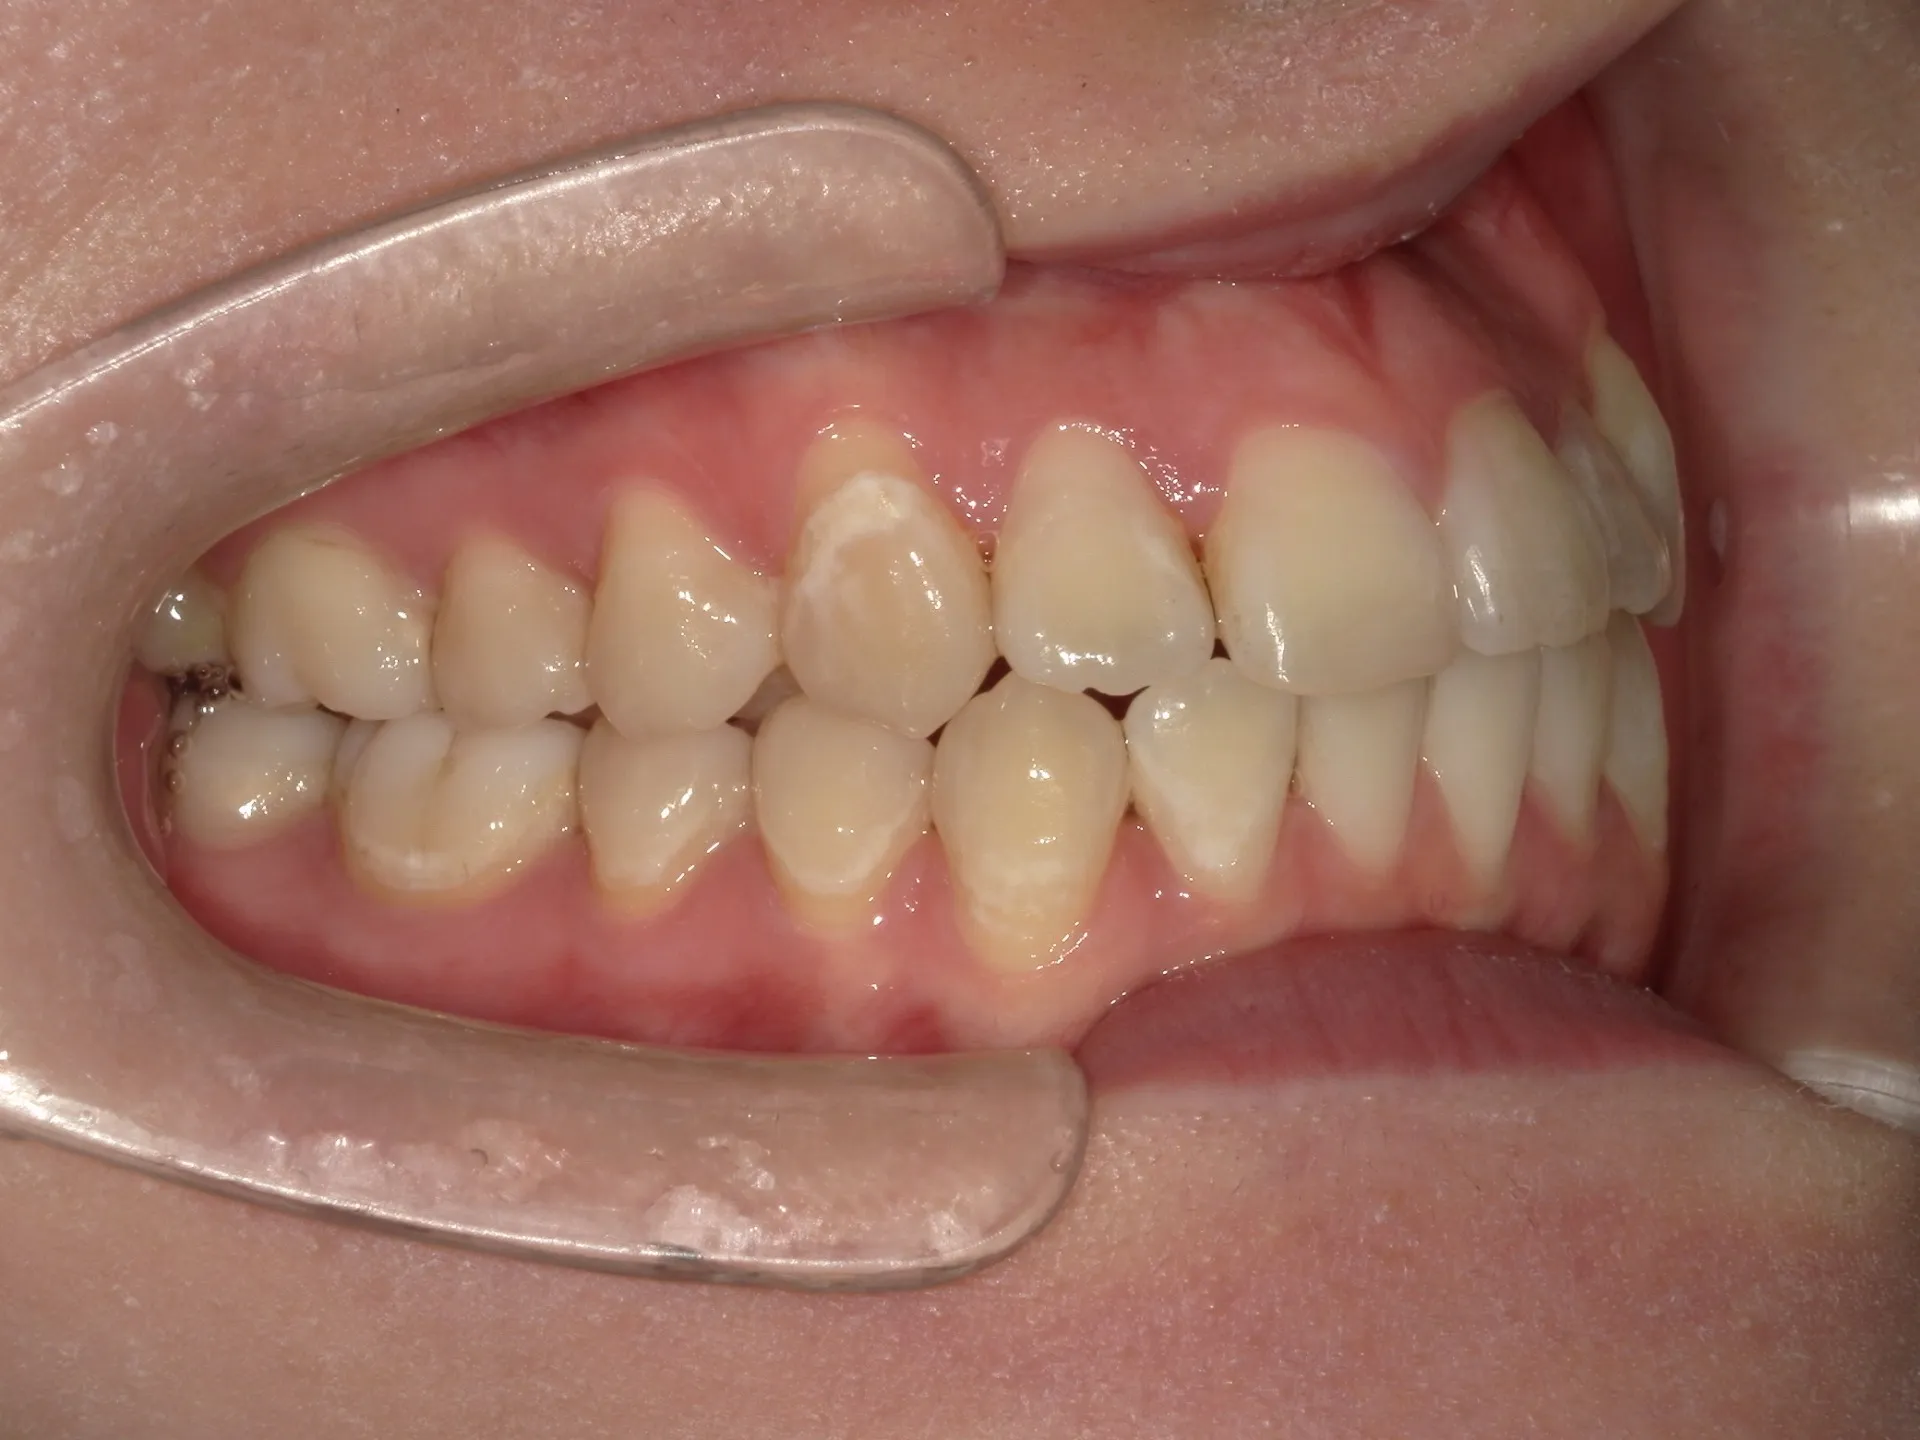

今回はマウスピース矯正で治療した八重歯の矯正についてご紹介いたします。

マウスピース矯正はワイヤー矯正と比較して軽度~中等度しか利用できないと言われることもあります。

どこまでが軽度でどこまでが中等度のガタツキなのかにもよりますが、治療前の歯並びであれば患者さんの協力も当然必要ですが、マウスピース矯正でも十分治療できることが分かります。